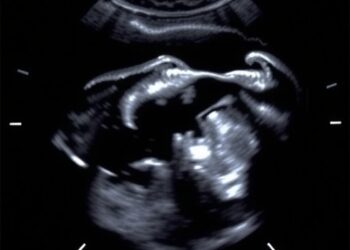

Exploring Non-Contrast Transperineal Ultrasound in Pediatric Care